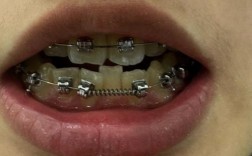

传统矫正中,结扎丝可能压迫口腔黏膜,导致溃疡或不适;而Damon托槽表面光滑,无结扎丝突出,配合低摩擦力机制,患者在治疗初期的疼痛感显著降低,且整个矫正过程更平稳。

(图片来源网络,侵删) -